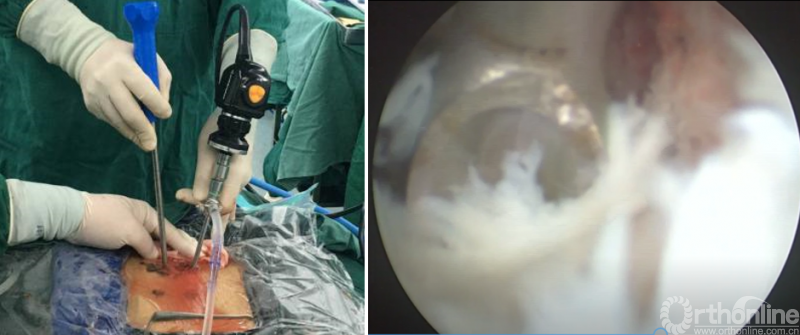

PE-PLIF技术十步法

详细步骤:一定、二辨、三凿、四分、五咬、六切、七旋、八铰、九填、十置

第七步“旋”:旋转舌形套管保护神经根;

第八步“铰”:盲视下可撑开铰刀置入,撑开并处理上下终板;

第九步“填”;椎间隙填塞植骨;

第十步“置”:置入融合器、经皮钉。